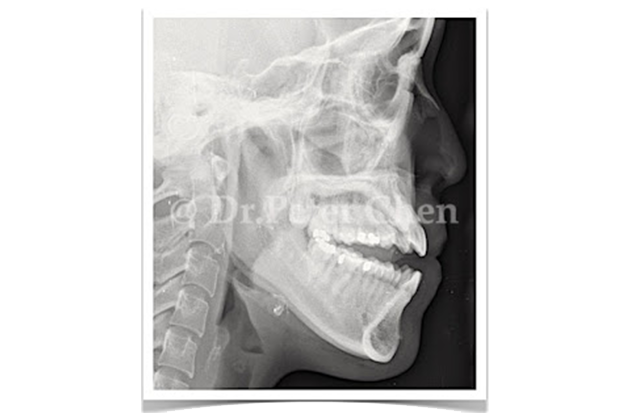

自 2000 年 隱形牙套問世後,矯正就不再是一個會破壞美觀的治療,隨著使用案例的增加,2005 年 Dr. Robert Boyd 發表 Invisalgin 配合 正顎手術治療 class III (戽斗)的案例

前牙開咬,對於許多人來說是種不討喜的咬合。一方面牙齒無法緊閉,說話一不小心就容易漏風,好像大舌頭;一方面嘴巴不易閉合,常常需要用到下巴的頦肌 ( mentalis muscle ),看起來好像在生氣。